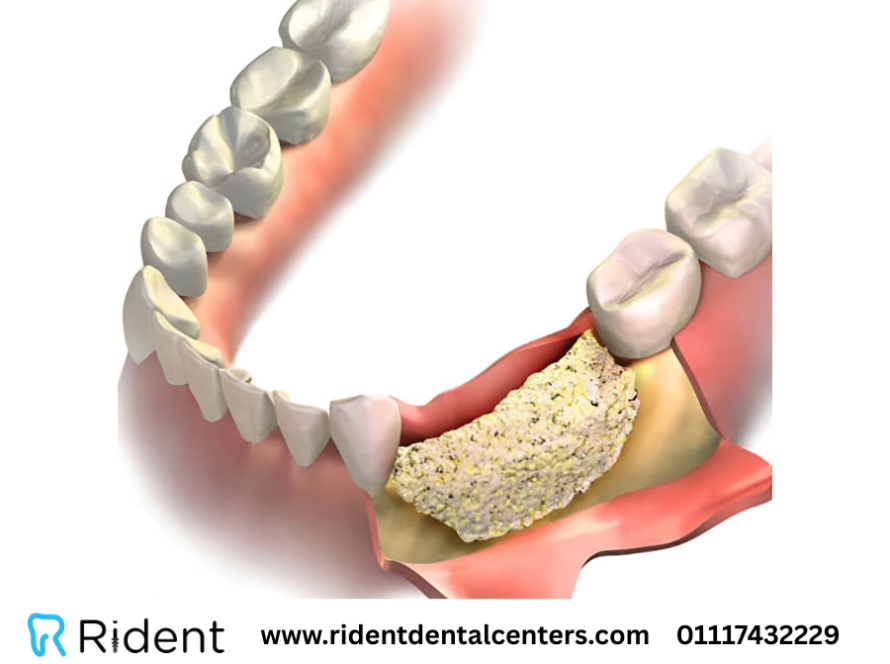

من المعروف لدى الكثير من الناس أنه يتم استخدام الجراحة في زراعة الأسنان عندما يقوم الطبيب بعمل شق جراحي حتى يتم زرع غرسة الأسنان بداخل عظام الفك لتحل محل الجذر قبل المرحلة الأخرى التي يتم فيها تركيب تاج السن الخارجي، ولكن هل توجد حالات في زراعة الأسنان لا يتم فيها ذلك؟ هذا ما سنعرفه في الفيديو.

يعبر مصطلح زرع الأسنان بدون جراحة عن وضع الغرسة مباشرة في قشرة عظام الفك بدون الحاجة إلى إجراء شقوق جراحية وخياطة وهكذا، وعادة ما يكون ذلك مناسباً بشكل خاص للحالات التالية: